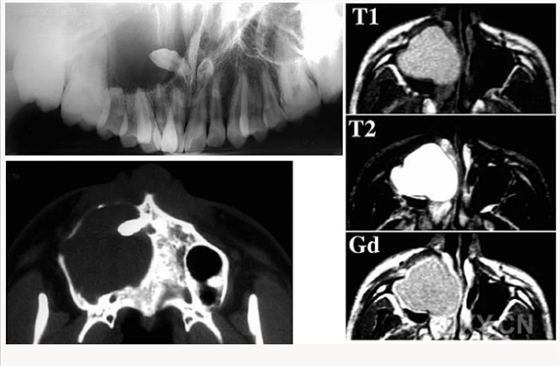

頜骨腫瘤

腺淋巴瘤[沃辛瘤